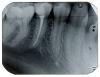

Чиффа Опубликовано 5 февраля, 2008 Поделиться Опубликовано 5 февраля, 2008 уважаемая Jusy! Разместите, по возможности, рентгеновский снимок вашего зуба. Тему перенесла в раздел "Пациентам". Ссылка на комментарий

Jusy Опубликовано 21 февраля, 2008 Автор Поделиться Опубликовано 21 февраля, 2008 Привет! Подскажите, пожалуйста, в данном случае как должна пройти подготовка зуба к установке коронки. Я имею в виду обточку зуба под коронку. Доктор мне сказал, что мне придется спилить этот зуб "под десну" и фактически полностью "наращивать" (sorry за возможную бредовость формулировки) зуб коронкой. Я хотела бы уточнить, это действительно необходимо судя по снимку? Или можно спилить чуть меньше? Просто мне кажется, что если практически весь зуб спилить и поставить коронку, то она будет плохо держаться и отвалится очень скоро. Я не права? Ссылка на комментарий